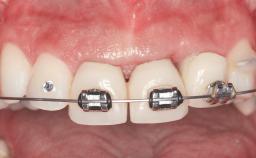

In 2001, a 48-year-old woman presented at a dental clinic with a failing fixed partial denture spanning from teeth 13 to 21. She was experiencing pain upon function, tenderness to palpation facial to tooth 13, and severe mobility of the prosthesis. Radiographic and clinical assessment revealed a subcrestal fracture of tooth 13, making its restoration unlikely. It was determined by the clinician that the tooth needed to be extracted prior to proceeding any further with dental care. After the extraction, the patient lost confidence in the progression of her treatment and sought consultation at the Center for Implant Dentistry. At her consultation visit in our clinic, an extra- and intraoral clinical examination revealed a medium lip line at full smile and an edentulous area spanning from 13 to 12 with both vertical and horizontal deficits in hard and soft tissue.

Prosthesis Type FDP

Loading Protocol Conventional or early

Retention Cemented, with prosthesis margin < 3mm submucosal Cemented, with prosthesis margin < 3mm submucosal

Interim Prosthesis during Healing Fixed Fixed